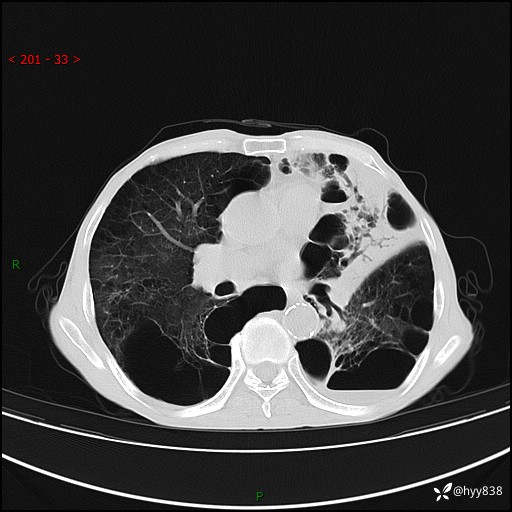

胸部CT平扫+增强